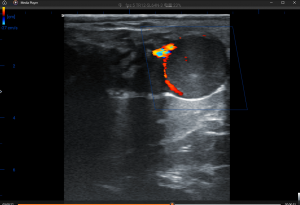

常规的B超(灰阶)需要在妊娠28天左右才能看到明显的羊水暗区或胚胎。而多普勒彩超技术提供了更早的判断依据:黄体血流。

多普勒原理: 多普勒彩超能够捕捉并显示流经血管的血液信号(以彩色显示)。

诊断依据: 在配种后21天,如果多普勒彩超显示黄体周围有强烈的彩色血流信号(即血流等级高),则可以高度确定母牛测奶牛妊娠成功。如果血流信号微弱或缺失,则提示未怀孕。